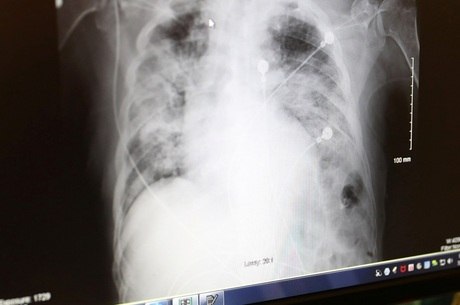

Pneumonia Necrotizante Medicinanet

Pneumonia Necrotizante Medicinanet from www.medicinanet.com.br